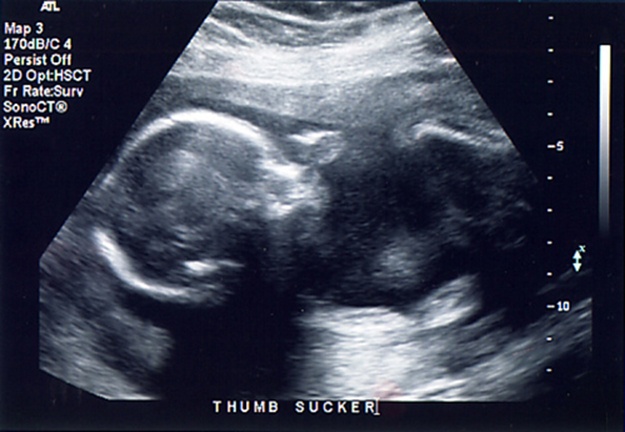

Any sound with a frequency above 20,000 Hz (or 20 kHz)—that is, above the highest audible frequency—is defined to be ultrasound. In practice, it is possible to create ultrasound frequencies up to more than a gigahertz. (Higher frequencies are difficult to create; furthermore, they propagate poorly because they are very strongly absorbed.) Ultrasound has a tremendous number of applications, which range from burglar alarms to use in cleaning delicate objects to the guidance systems of bats. We begin our discussion of ultrasound with some of its applications in medicine, in which it is used extensively both for diagnosis and for therapy.

The characteristics of ultrasound, such as frequency and intensity, are wave properties common to all types of waves. Ultrasound also has a wavelength that limits the fineness of detail it can detect. This characteristic is true of all waves. We can never observe details significantly smaller than the wavelength of our probe; for example, we will never see individual atoms with visible light, because the atoms are so small compared with the wavelength of light.